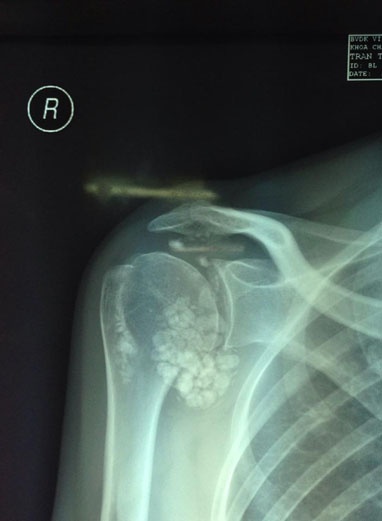

| Hình X-quang ổ sỏi trong vai phải của bệnh nhân - Ảnh do BS Nguyễn Trọng Anh cung cấp. |

Êkip phẫu thuật đã nội soi. Sau hai giờ, 107 viên sỏi được gắp ra có kích thước 1mm-1,5cm, hình thành do bệnh u sụn hoạt mạc khớp vai, gồm tăng sinh nhú hoạt mạc, thoái hóa sụn khớp và tạo nhiều sỏi trắng trong khớp. Bệnh nhân mổ xong sẽ bớt đau nhưng vẫn phải dùng thuốc và theo dõi kỹ.